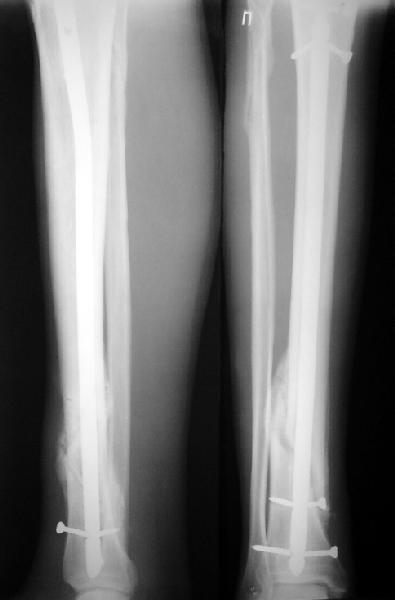

По крайней мере ходящих без дополнительной опоры через 1 месяц после операции с небольшой - при изолированной травме немало. Нестабильные по оси, кстати, не только оскольчатые, но и спиральные.

И если пациент еще не возвращается к полной нагрузке и функции, то не потому, что не разрешает врач, опасаясь несостоятельности фиксации.

Как мне показать пример? Фото стоящего на одной оперированной конечности пациента? O! Пример, подвигнувший нас на некоторое изменение технологий. Пациент этот ходил с полной нагрузкой вопреки рекомендациям. В качестве подтверждения - сломанный проксимальный статический винт к 1 мес., а к 2 мес. - все остальные. Сейчас мы перешли на более fool-proof остесинтез.

Это наглядная демонстрация возможности ранней полной нагрузки при нестабильном по оси повреждении, причем не в самых благоприятных механических условиях - при плохом сопоставлении, со слабым фиксатором.

Как я уже говорил, мы сделали выводы из этого и других подобных случаев. Очевидно, решений проблемы два - либо уменьшить нагрузку, либо увеличить прочность фиксатора. Первое решение работает не со всеми больными, так что пошли по второму пути - мы больше не используем гвозди с запирающими винтами диаметром 4 мм.